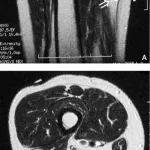

8時前に病棟に上がって, 昨日後輩医師の執刀で関節鏡下外側半月板縫合術が行われた高校生の患者さんの経過を確認.

15時に手術部に移動し, 手術を執刀.

胸部に生じた脂肪腫の摘出術でした.